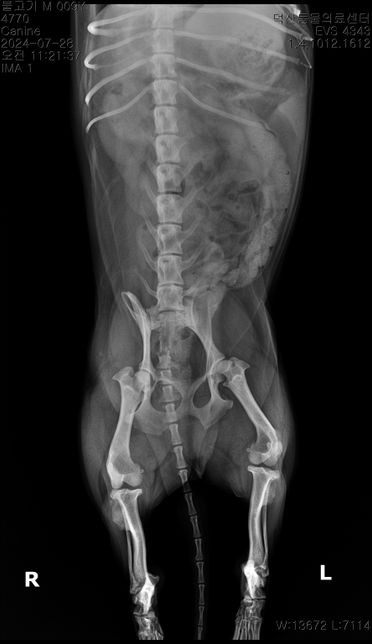

- 반려동물 건강반려동물Q. 순차적으로 고관절 에 관해 봐주시기 부탁드립니다.3 사진이 순차적입니다 순차적으로 고관절에 큰 변화가 있나요?마지막 보여지는 부분에서 오른쪽 고관절이 탈구된거라고 하는데 이전 사진에서는 탈구가 안되었나요?